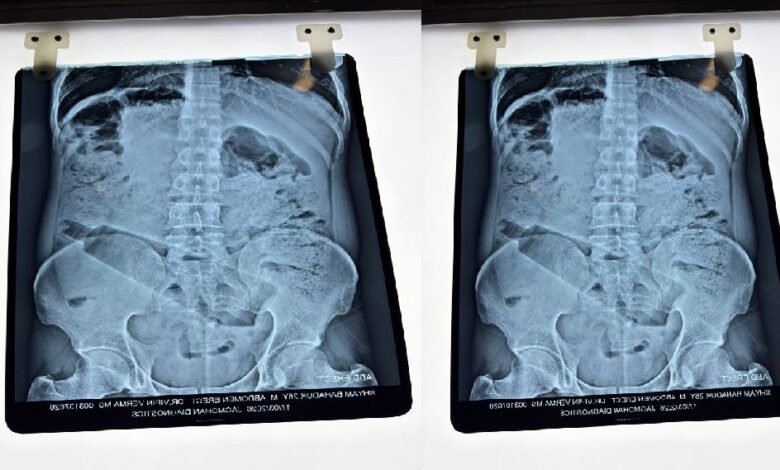

उत्तर प्रदेश के अम्बेडकरनगर जिले के अकबरपुर क्षेत्र पटेलनगर से एक चौंकाने वाला मामला सामने आया है। एक युवक ने नशे की हालत में अपने प्राइवेट पार्ट में प्लास्टिक की बोतल डाल ली। कुछ समय बाद पेट में तेज दर्द उठने पर वह अस्पताल पहुंचा, जहां जांच में सच्चाई सामने आई।

डॉक्टरों ने ऑपरेशन कर पेट से बोतल निकाली और युवक को राहत दी। बता दें कि इसी तरह का एक मामला कुछ दिन पहले आगरा से भी सामने आया था, जहां एक युवक ने यौन उत्तेजना में बोतल डाली थी और सर्जरी के बाद ठीक हुआ।